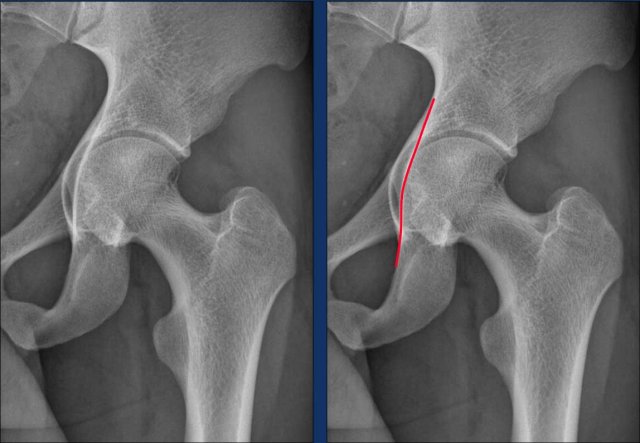

Alpha angle measurement

The normal hip shows an alpha-angle far below 60º.

The hip with the Cam morphology has an alpha-angle far above 60º.

Of course, when the Cam morphology is as pronounced as in this case, angle measurements are unnecessary.

This is a more subtle case of Cam morphology in a young male.

Notice that the epiphyseal plates have not yet closed (arrow).

Images

Two examples of Cam morphology.